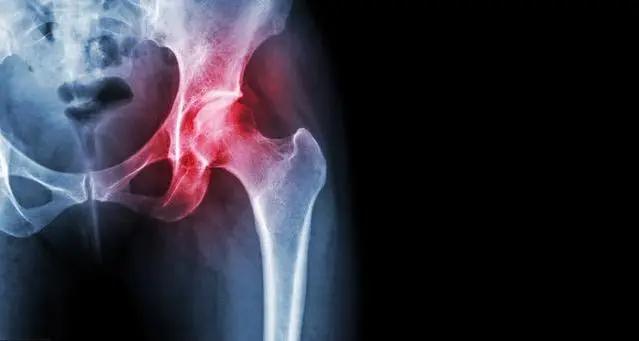

股骨头坏死是不是无法根治?股骨头坏死为什么一直治疗不好?股骨头坏死如何治疗好?

网上有关股骨头坏死的问题被网友频繁搜索,有关于股骨头坏死的治疗,每个患者的病情不一样,治疗方法也不同,但是,治疗后股骨头的恢复却是有共同的原则的,今天我们就一起来了解下股骨头坏死必经的恢复阶段。